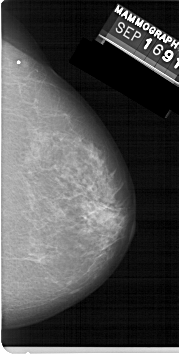

A_1224_1.RIGHT_MLO

RIGHT_MLO LINES 5491 PIXELS_PER_LINE 2926 BITS_PER_PIXEL 12 RESOLUTION 43.5 NON_OVERLAY